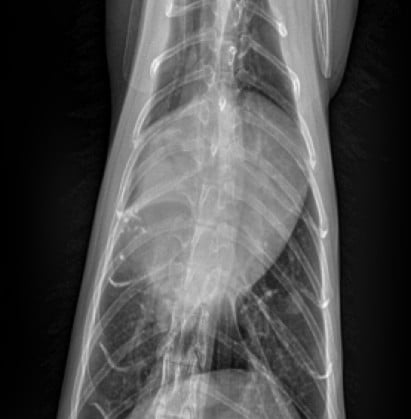

심장질환으로 인한 급성호흡곤란, 폐수종, 쇼크 등 응급 상황에 신속하고 체계적으로 대응합니다. 환자의 증상과 상태에 따라 맞춤형 응급처치 프로토콜이 즉시 적용됩니다.

심비대, 폐수종, 심부전까지 유발할 수 있는 질환.